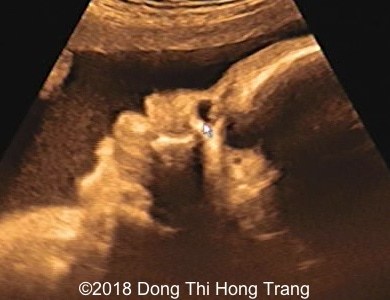

Images 1 and 2; videos 1, 2 and 3: 2D and Doppler images of lacrimal anechoic sac, compatible with dacryocystocele.

Image 1